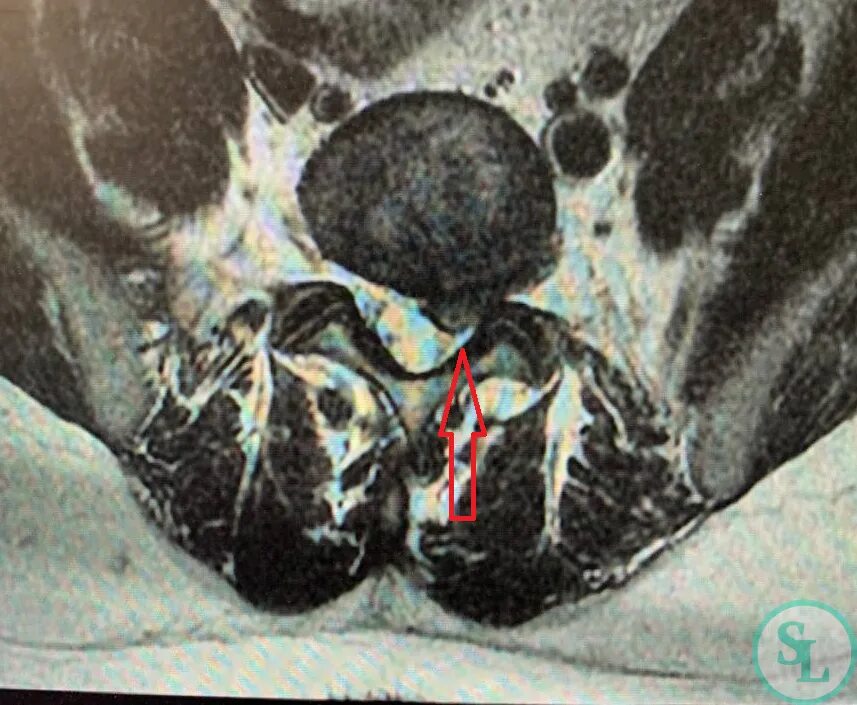

Грыжа экструзия диска l5 s1